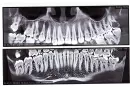

Недавно у меня случайно обнаружили большую кисту (на верхней челюсти), которая уже разрослась на три зуба: 5-й, 4-й и частично на 3-й.

Увидев этот ужас, врач отправил меня на плановую операцию в стационар челюстно-лицевой хирургии. Параллельно я обращалась к двум хирургам. Все они говорят, что зубы спасти не получится, нужно удалить все три зуба и вставлять импланты.